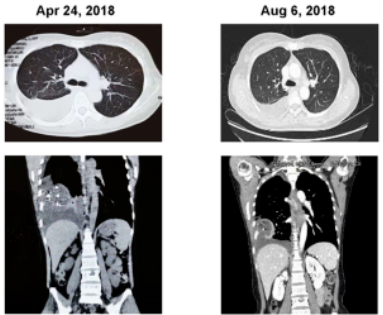

63岁的M先生被确诊晚期肺腺癌,同时伴有纵隔淋巴结转移和双肺转移,进行基因检测后发现了一种非常罕见的PRDX1 - NTRK1融合。患者先接受了克唑替尼的治疗,一个月后达到部分缓解,胸腔积液消失。克唑替尼治疗4个月后,M先生又接受了5个月化疗。2019年,M先生幸运的入组了全球首款上市的NTRK抑制剂拉罗替尼在中国的临床试验,免费的用上了这款传奇抗癌药。2019年5月,在接受治疗后仅2个月的评效显示,肿瘤再次显著缩小,达到部分缓解,并且产生了持久的缓解!

晚期纤维肉瘤

42岁的W女士在2009年确诊为晚期梭形细胞纤维肉瘤,随后的9年里,她接受了多种治疗方案,但病情仍未得到有效控制。2018年3月,基因检测结果显示W女士存在非常罕见的LMNA-NTRK1融合,幸运的入组了拉罗替尼的临床试验后仅2个月,病情就得到了有效控制。